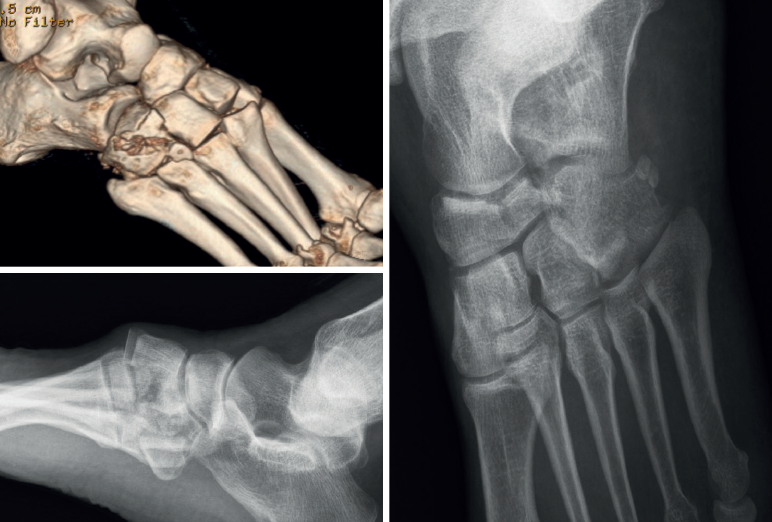

Las fracturas en cascanueces del cuboides (nutcracker's fracture) son lesiones infrecuentes que pueden pasar desapercibidas en su valoración inicial(1). En general, la incidencia anual de las fracturas de cuboides se sitúa en torno a 1,8/100.000 casos(2). En la literatura encontramos escasa evidencia científica basada en series de casos retrospectivas de tamaño muestral pequeño, siendo la serie más larga publicada de 16 pacientes, en las que apenas se hace mención acerca de su complejidad y frecuente asociación con otras lesiones en el pie(3). Generalmente, son ocasionadas por una compresión axial entre la base de los metatarsianos cuarto y quinto y el cuboides tras fuerzas de flexión plantar(4). Un aspecto destacable de este tipo de fracturas es el acortamiento de la columna lateral del mediopié secundario al colapso del cuboides por la fractura y su consecuencia en la biomecánica del pie(1). En ocasiones es posible ver en una radiografía la imagen “en nuez cascada” (cracked walnut) consecuencia de la fractura del cuboides (Figura 1). El objetivo del presente trabajo fue analizar una serie de pacientes con fracturas en cascanueces de cuboides en función de las lesiones asociadas detectadas, el manejo realizado, los resultados obtenidos y las complicaciones observadas, siendo esta serie la segunda más larga publicada en la literatura revisada.

La edad media de la serie presentada es de 45 años (rango: 21-69 años). El seguimiento medio fue de 22 meses (rango: 12-65 meses). El mecanismo de acción de las fracturas fue, en 7 casos (53,8%), un traumatismo de alta energía tras accidente de tráfico, y, en los 6 casos restantes (46,2%), caída casual asociada a torsión de tobillo. Ninguna de estas fracturas se diagnosticó de forma aislada (Figura 2), objetivándose fractura de la pars anterior y cuerpo de calcáneo en 6 casos (46,2%), fractura de escafoides tarsiano en 4 casos (30,8%), en 2 casos (15,7%) lesión del complejo ligamentoso de Lisfranc y 1 caso (7,6%) de fractura-luxación de la base de los metatarsianos cuarto y quinto (Tabla 1).